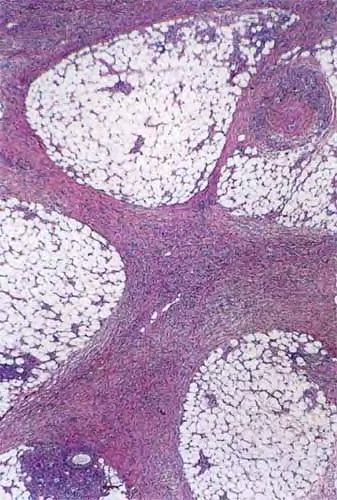

Histopathologically, the signature cell of ENL is the neutrophil, which may be abundant, scant, or absent, if an old lesion is sampled . Other common features include an increase in lymphocytes, a thickened epidermis, and a lobular panniculitis. Vasculitis is uncommon. The usual histologic pattern is a “bottom heavy” infiltrate, preferring the deep dermis and subcutis.